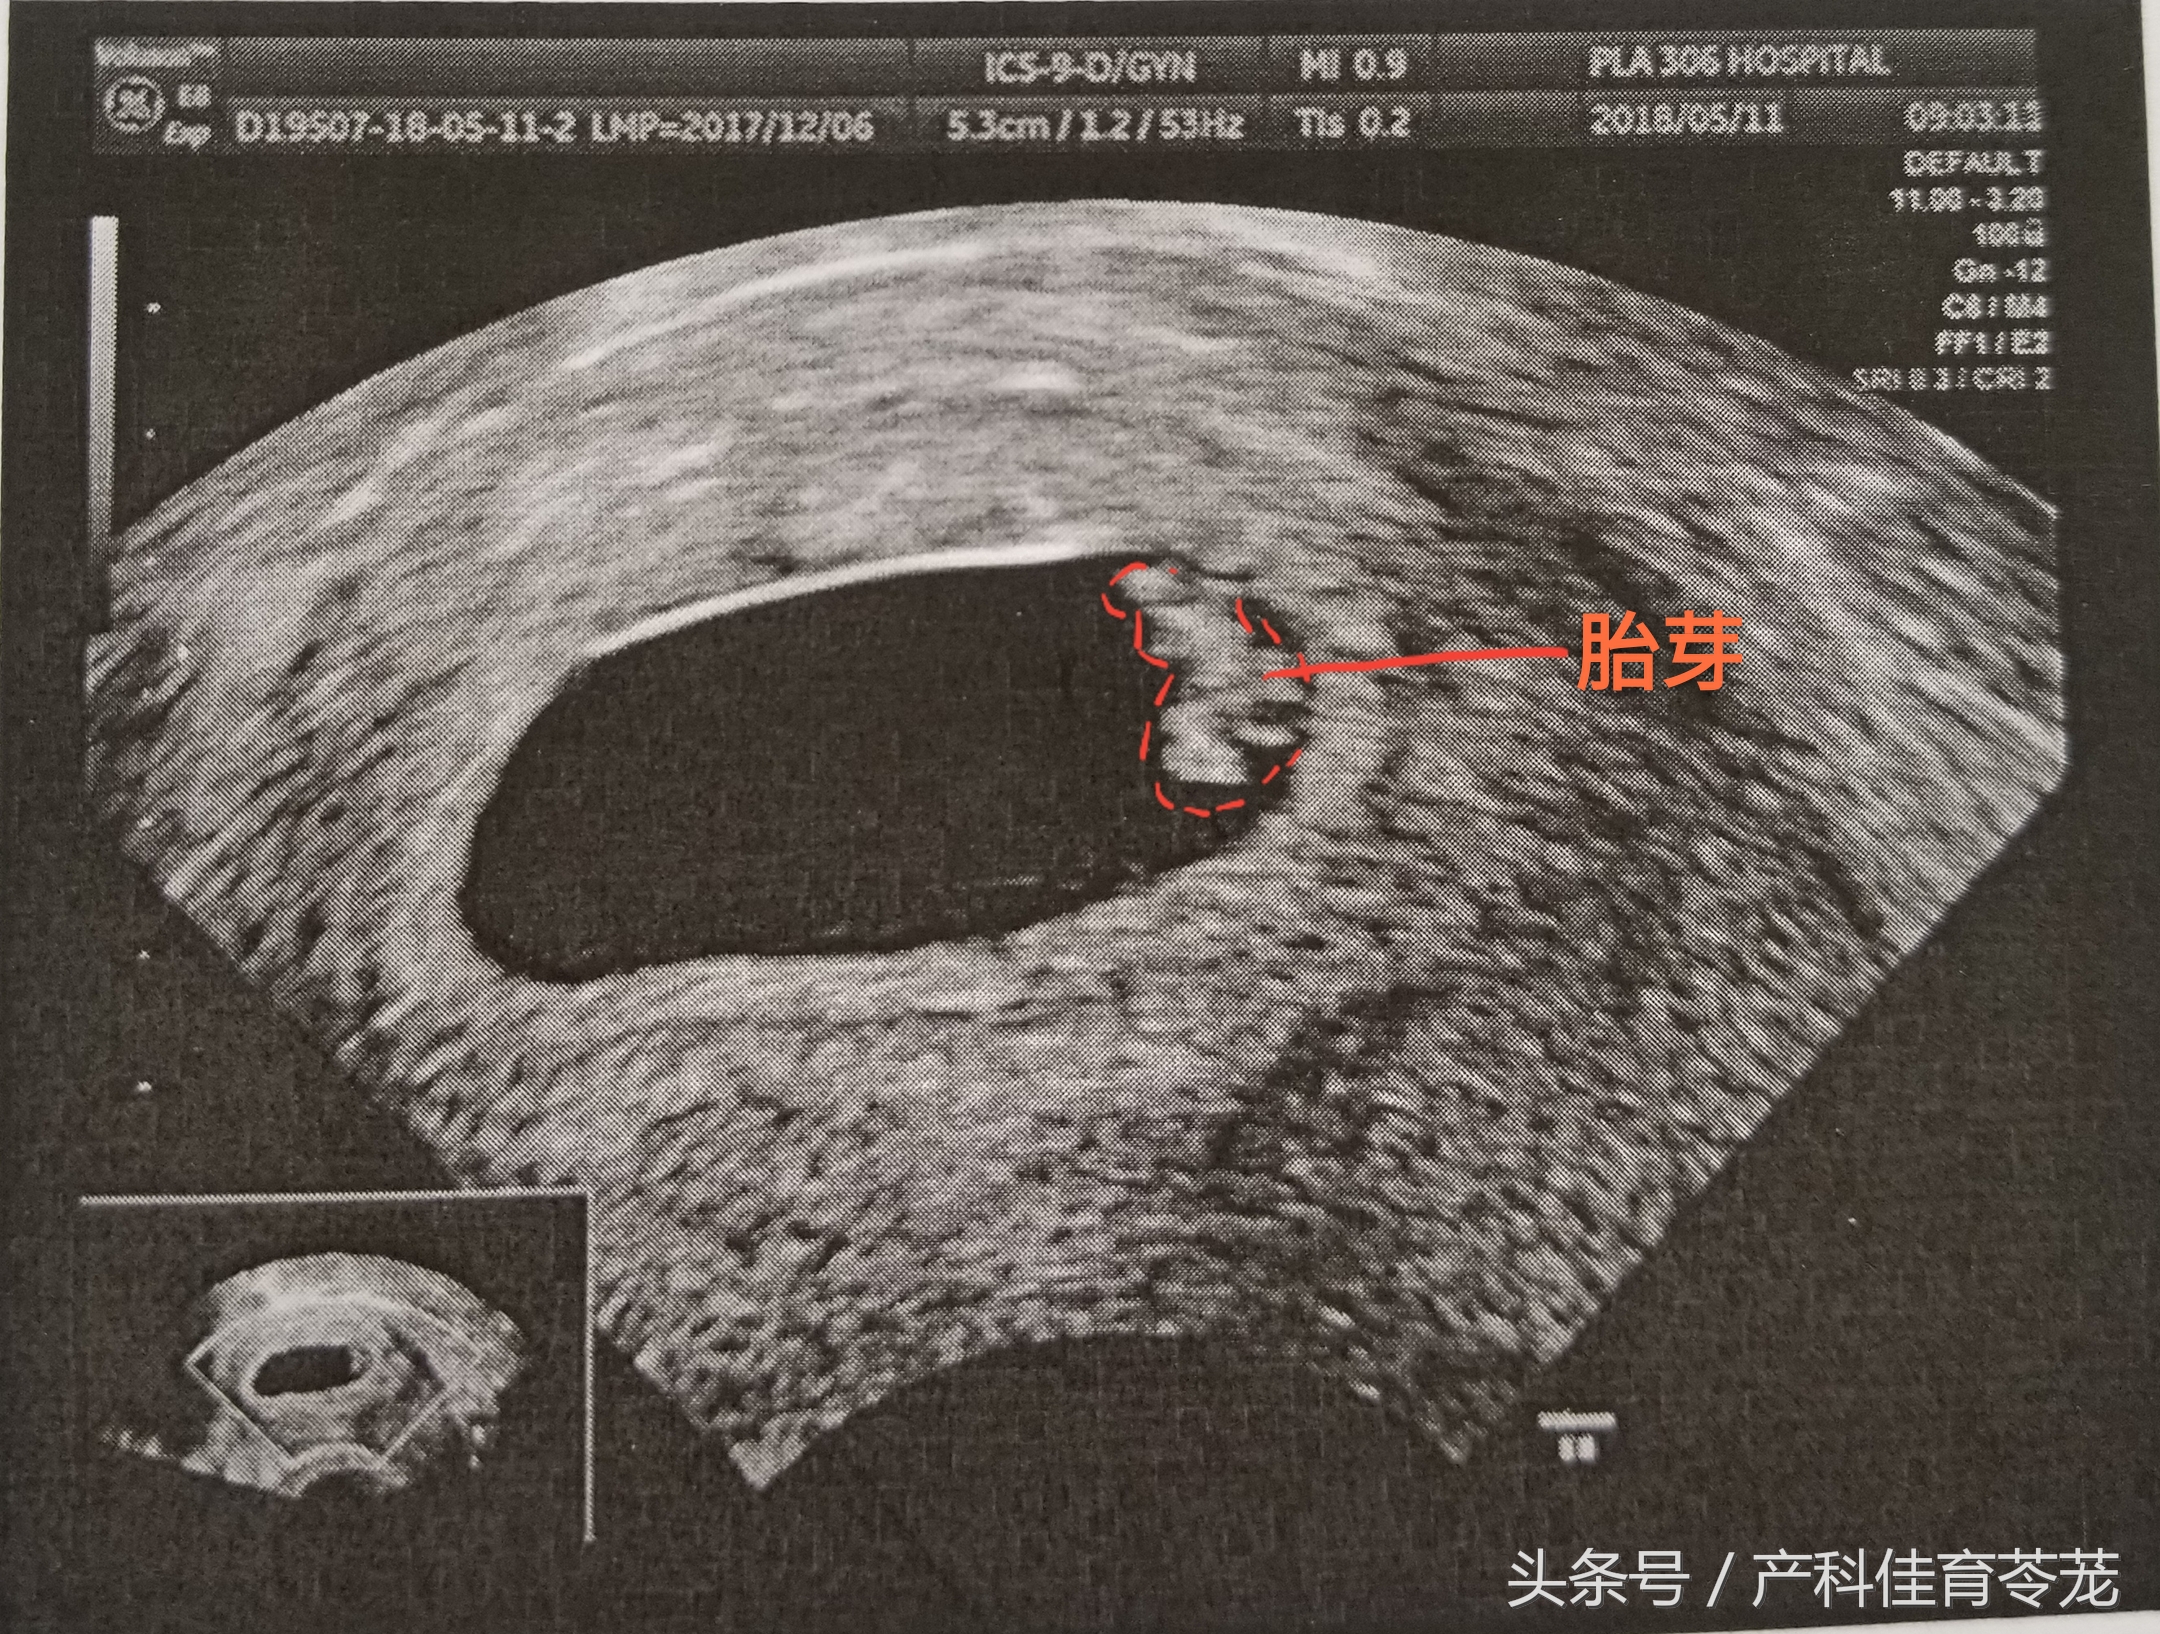

三、胎芽(Fetal Pole)

只有出现胎芽,才能明确是宫内妊娠。

胎芽的增长速度为1mm/d,到妊娠53天时可以长到12mm。

胎芽长度达2mm或以上就可以看到胎心搏动,但也有5-10%的2-4mm的胚胎仍然看不到明显的胎心搏动。

胎芽的长度可以用来推算妊娠时间,准确率在3天之内:

妊娠天数=胎芽长度(mm)+42